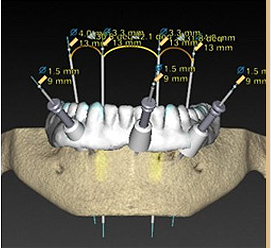

锥形束平板CT:

360°3D口腔透视

CT数据+种植医生

+3D种植模拟软件

智能导航,3D种植导板定位

不翻瓣、3-4mm

微孔植入

数字化3D导板定位植体深度、角度,微孔植入创口牙根大小